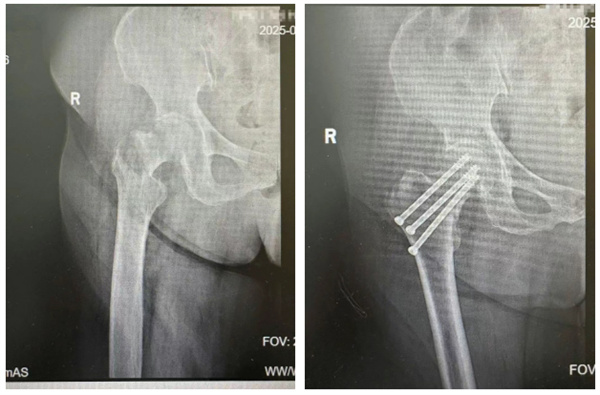

6月下旬,80岁的史奶奶因意外造成右侧股骨颈骨折。7月,其在外院接受了“右侧股骨颈骨折内固定术”,术后第3天便因康复需求转至我院康复医学科。

▲ 左图为患者骨折后X片;右图为患者行右侧股骨颈骨折内固定术术后X片

不同于常规术后患者,史奶奶的病情清单上标注着诸多“红色警示”:外院手术记录显示术中曾出现血压波动,最终放弃关节置换改为闭合复位内固定;骨密度检测提示重度骨质疏松,内固定物犹如在“松软沙地”中立足;既往癌肿手术史让心肺功能耐受性存疑,部分物理治疗手段受限;更棘手的是,老人因对病情过度担忧,出现明显焦虑抑郁情绪,不仅拒绝服用任何药物,对康复训练也极度恐惧、抵触配合。